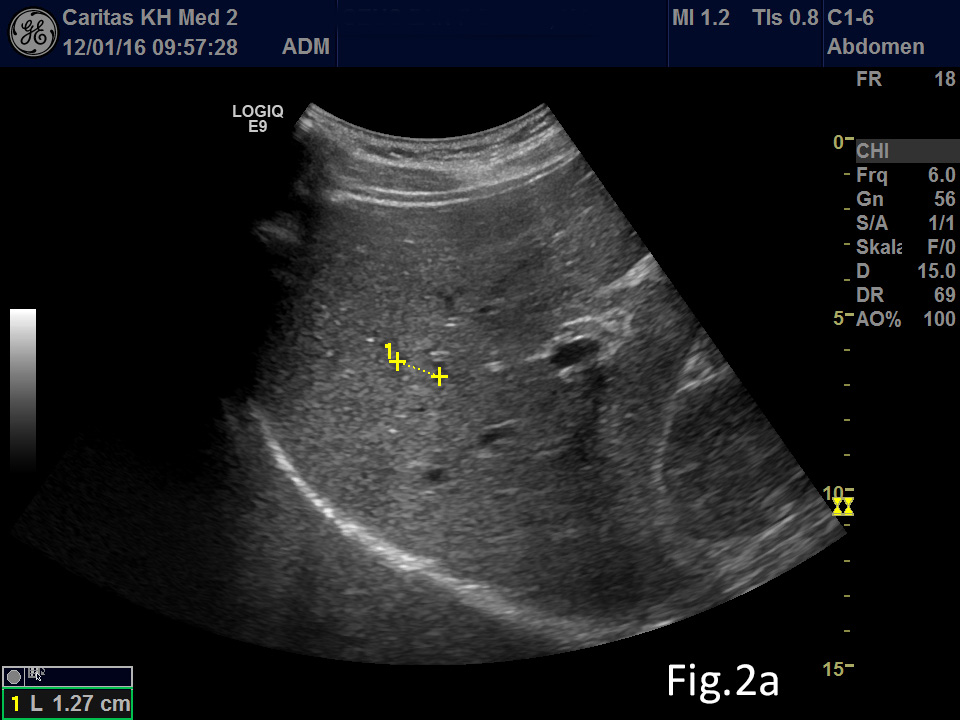

We report on a 28 year old male presenting with unspecific abdominal pain for two weeks. B-mode ultrasound revealed extended abdominal lymphadenopathy [Figure 1] and two small unspectacular hemangioma-like focal liver lesions [Figure 2]. The left testis revealed a palpable tumour by ultrasound also examined with elastography and contrast enhanced ultrasound [Figure 3 and 4]. Endoscopy of the upper gastrointestinal tract showed candida of the esophagus. The biopsy of the abdominal (retroperitoneal) lymph nodes revealed epithelial cells, typical for testicular embryonal cell carcinoma.

Figure 2: Focal liver lesion using B-mode (a) and contrast enhanced ultrasound (CEUS) in the arterial (b), late phase (c) and CEUS using time intensity curve analysis (TICA) (d). The B-mode ultrasound showed an isoechoic lesion with transducer distal shadowing, somewhat unspectacular. CEUS showed early and slightly hyperenhancing features in the arterial phase and pronounced wash out in the portal venous and late phases indicating metastases and excluding hemangioma [(1)]. The TICA image on the right side of the screen differentiates the initially hyperenhancing lesion (red line) in comparison to the surrounding liver parenchyma (yellow line). In the portal venous phase the red line crosses downward in comparison to the liver parenchyma (yellow line), indicating metastasis [(2-5)].